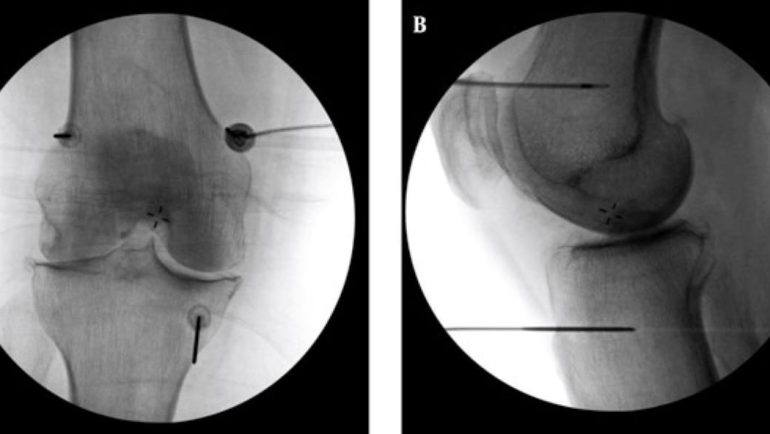

高頻熱凝療法以X光定位將電極導針導引至膝蓋的三個主要感覺神經叢,藉由熱能與電效應,麻痺痛覺神經。(台北慈濟醫院提供) 記者蔡琇惠∕新北報導 85歲黃先生患有退化性膝關節炎超過10年,長年來嘗試藥物治療、復健、關節內注射類固醇與玻尿酸、自費療程等多種非手術治療,效果皆有限,甚至需服用高劑量止痛藥控制疼痛,來到台北慈濟醫院就診時只能依靠輪椅代步。骨科醫師李宜軒評估其狀況已符合換人工關節的條件,但考量年紀及手術風險,黃先生還是優先考量其他治療及止痛方式。最後李宜軒以「高頻熱凝療法」緩解其疼痛,治療一週後,疼痛減輕七至八成,也順利恢復行走能力。 根據台灣統計,退化性關節炎盛行率隨年齡增加而升高,60歲以上國人約有半數受影響,且有年輕化趨勢。李宜軒指出,現今50歲就出現膝關節骨刺或關節磨損的患者數量提升,多與不正確的運動姿勢、劇烈運動造成的過度磨損,或完全缺乏運動、肌肉萎縮有關。疾病初期症狀多以關節出現「喀拉喀拉」的摩擦聲響、長時間站立或行走後痠軟為主,中期會出現活動時疼痛、關節活動度下降,進入中後期,疼痛甚至在休息時也持續存在。晚期患者由於膝關節軟骨已完全磨損,骨頭與骨頭直接摩擦,即可能面臨膝關節提早退化。 診斷上,退化性關節炎可透過X光查看軟骨縫隙、有無骨刺等,結合身體檢查觀察關節的穩定度、疼痛情況以及是否積水,藉此評估退化程度。原則上,中度以前多能藉由藥物、復健、肌力訓練、生活調整與體重控制改善,中晚期的患者則可能需要置換人工關節,但針對不適合手術或不願手術的患者,則可採用「高頻熱凝療法」止痛。 李宜軒說明,此項技術過往多用於椎間盤突出、滑脫等脊椎神經壓迫造成的下背痛、坐骨神經痛的止痛治療,近來也運用至膝關節退化。執行方式是在局部麻醉的情況下,以X光定位將電極導針導引至膝蓋的三個主要感覺神經叢,確認施行目標後,接上電源線輸出高頻電波,藉由熱能與電效應,使引起疼痛的神經失去傳導疼痛的能力,降低疼痛。 為確保施行過程中未傷及運動神經,治療前會進行不同電量測試,並請病人活動膝蓋,在確定不影響日後活動的情況下進行治療。一般而言,效果會在術後當下至一週內顯現,普遍可維持半年至一到兩年,因人而異。 膝蓋要使用一輩子,李宜軒呼籲,民眾平時可透過游泳、騎腳踏車、股四頭肌運動或瑜珈等低衝擊運動維持腿部肌耐力和關節功能。若膝關節出現不適應盡早就醫,切勿拖延至晚期或自行尋求未經驗證的民俗療法,以免錯過治療良機。